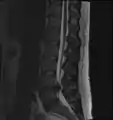

- Magnetic resonance imaging (MRI) without contrast is a diagnostic test that produces three-dimensional images of body structures using powerful magnets and computer technology. It can show the spinal cord, nerve roots, and surrounding areas, as well as enlargement, degeneration, and tumors. It shows soft tissues better than CAT scans. An MRI performed with a high magnetic field strength usually provides the most conclusive evidence for diagnosis of a disc herniation. T2-weighted images allow for clear visualization of protruded disc material in the spinal canal.

MRI scan of large herniation (on the right) of the disc between L4 and L5 vertebrae

A rather severe herniation of the L4–L5 disc

Example of a herniated disc at L5–S1 in the lumbar spine